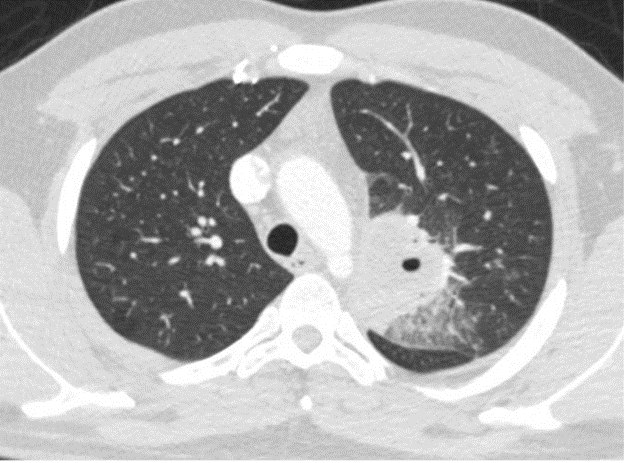

Case Presentation: Case: A 27-year-old male presented to the emergency room with fever, night sweats, and productive cough with brown sputum for the past week prior to presentation. He also noted associated anorexia, nausea, and non-bilious, non-bloody vomiting. The patient reported persistent dysphagia that had developed after his laryngeal schwannoma resection 15 years ago. On presentation, he was febrile to 100.4 degrees Fahrenheit, tachycardic to 102 beats per minute, and tachypneic to 37 breaths per minute. Physical exam was within normal limits. Labs were notable for neutrophil-predominant leukocytosis (WBC: 14.37 × 109/L) and elevated inflammatory markers. Computerized tomography of the chest demonstrated a focal necrotic air-filled lesion in the posterior left upper lobe consistent with lung abscess. The patient was admitted for management of lung abscess with parenteral antibiotics. He was started on ampicillin-sulbactam and demonstrated substantial clinical improvement. Sputum cultures grew normal respiratory flora. Videofluoroscopic swallowing study demonstrated moderately compensated oropharyngeal dysphagia. His course was complicated by drug-induced liver injury secondary to ampicillin-sulbactam and was switched to a four-week course of levofloxacin and metronidazole. He was discharged with close follow-up with his primary care provider, otolaryngology, pulmonology, and speech and language pathology.